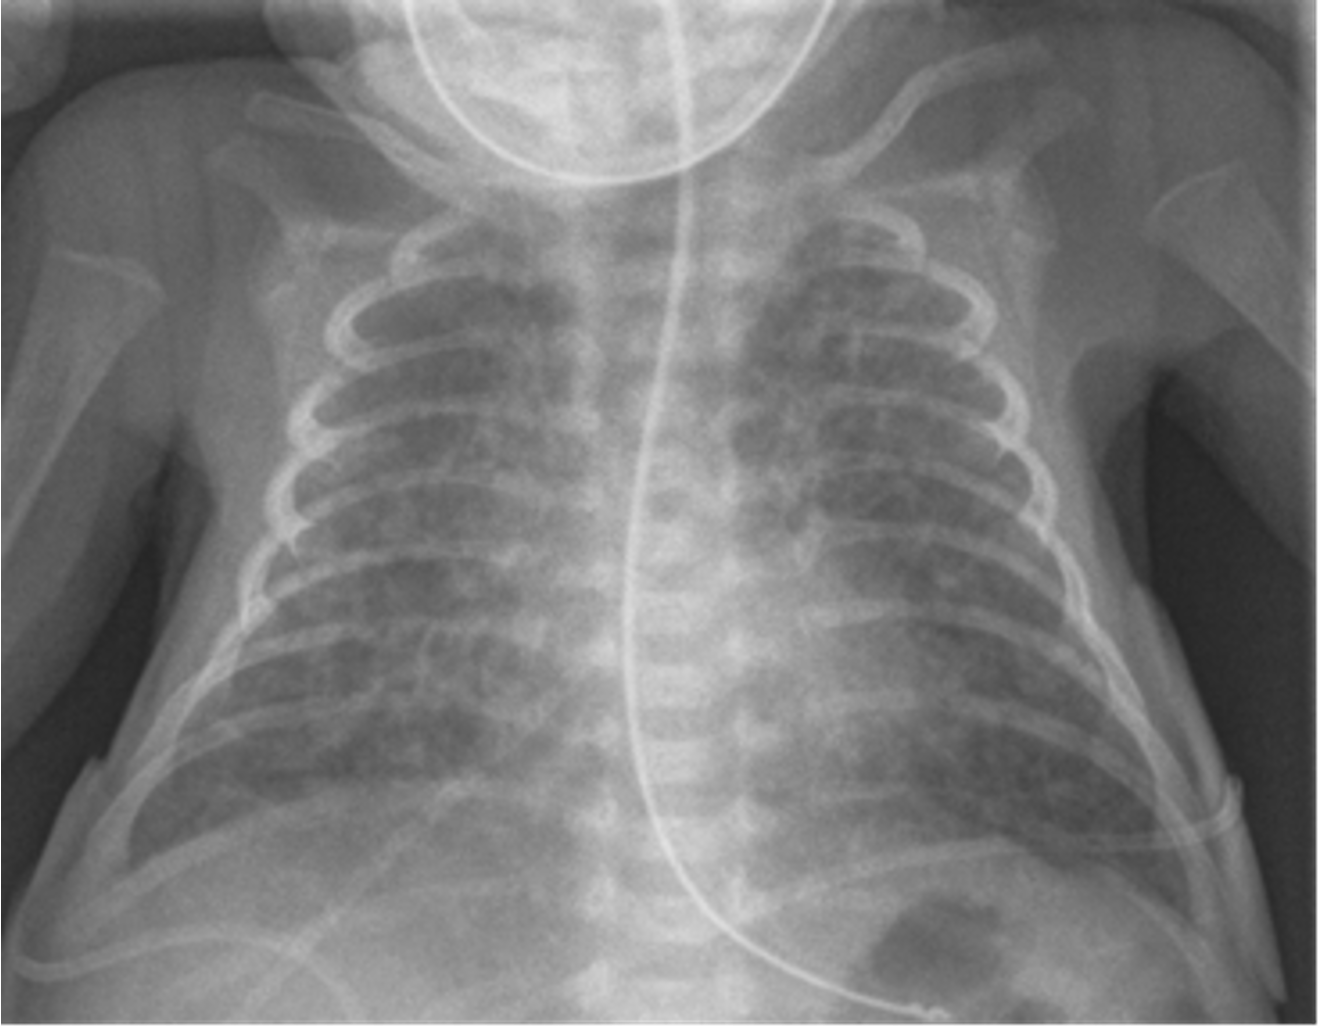

A preterm infant born at 25 weeks gestation is now 6 weeks old. The infant has been stable for the past few weeks, breathing in room air, and receiving full enteral feedings that consist of fortified maternal breast milk and some formula supplementation. Yesterday, the infant had a few large gastric residuals with feeding but was otherwise well. Today, you were called for a new onset of apneic spells, increased abdominal distension, poor urine output, lethargy, and hypothermia.

What is your spot diagnosis? necrotizing enterocolitis

- Dilated loops,

- thickened bowel walls,

- pneumatosis intestinalis (air in intestinal walls),

- pneumoperitoneum; indicate perforation (emergency requiring surgical intervention),

- portal gas (present in the portal venous system,

- considered to be a poor prognostic sign).

Further Deterioration

Despite your treatment, the patient deteriorated and was admitted to the NICU.

- What is your action? immediate surgery

inflamed, necrosis ⇒ Perforation everywhere

dark circles air in intestinal wall

Air in portal gas